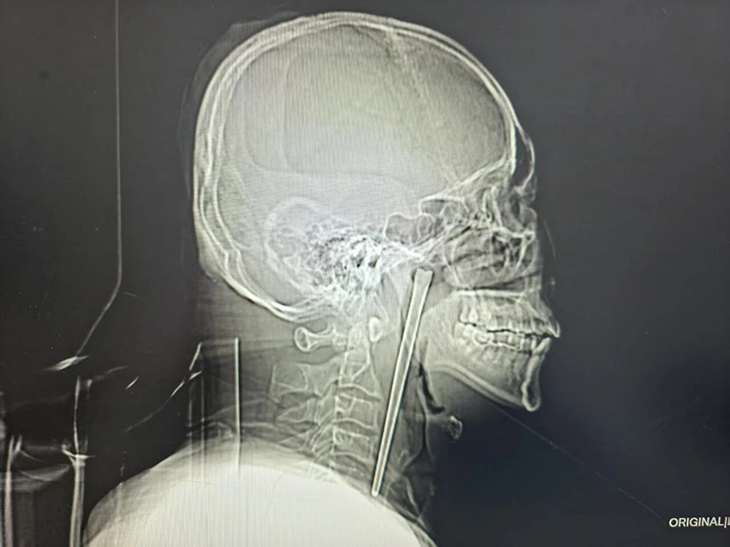

46-year-old Mr Wang recently showed up at the Dalian Municipal Central Hospital in Liaoning Province complaining about unbearable pain in his throat and a foreign body sensation. Following an X-ray exam, doctors were shocked to see a 12-centimetre shaft stuck in the patient’s throat, but when they asked him if he knew anything about it, he casually told them that it was a metal chopstick he had accidentally swallowed eight years earlier.

Eight years ago, Mr. Wang accidentally swallowed a whole metal chopstick while eating. He didn’t go into specifics about how exactly it happened, but an article on the Dalian Hospital website mentions that the Chinese man used to have an alcohol problem. Although he experienced a choking sensation in his neck and intermittent throat pain immediately after choking, he had no difficulty breathing.

The medical staff came up with a minimally invasive surgical plan for oral removal, eliminating the need for neck surgery and completely alleviating the patient’s concerns. Through minimally invasive surgery, Dr. Huang Weipeng gradually peeled and pulled the object, ultimately removing the 12-centimetre-long stainless steel chopstick intact.